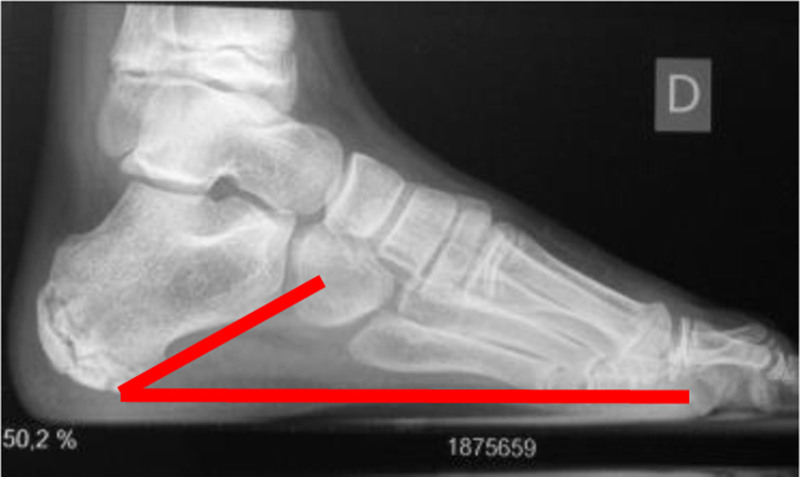

The objective of this study is to describe and evaluate dorsal hemiepiphysodesis of the first metatarsal as an osteotomy replacement technique. Retrospective analysis of patients with pes cavovarus (PCV) treated in our center with dorsal hemiepiphysodesis of the first metatarsal. Meary's angle, calcaneal pitch, and Moreau Costa Bartani were compared pre and post-operatively and the ratio between width and foot length was monitored. Between May 2012 and May 2022, eight patients (14 feet) with PCV underwent dorsal hemiepiphysiodesis of the first metatarsal combined with the Steindler procedure. Four patients (50%) were male. The average age for boys at surgery was 10.75 years (10-11) and for girls was 9.75 years (8-11). Most patients (87.5%) had idiopathic PCV and 12.5% had a neurological PCV. Median follow-up was 4.3 years (1.5-10) and a benefit was seen in all patients in Moreau Costa Bartani angle (112.64° vs. 120.59°; P value = 0.003), calcaneal pitch (26.48° vs. 25.36°; P value = 0.091) and Meary's angle (10.60° vs. 5.36°; P value = 0.008) after surgery. Supination improvement was also shown (0.21 vs. 0.24; P value = 0.039). Despite the limited number of patients, the results demonstrated that dorsal hemiepiphysiodesis of the first metatarsal can be a valid alternative to osteotomy of the base of the first metatarsal, with less morbidity and a gradual and dynamic correction throughout growth.

Abstract Image